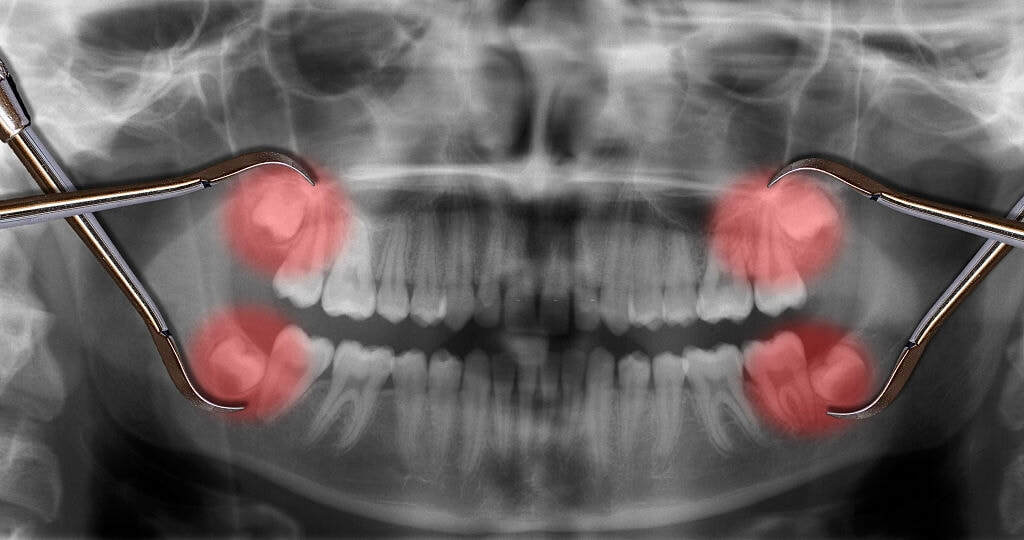

Most adults would agree that a toothache is an intensely painful and distressing experience. This severe discomfort can interfere with essential functions such as eating, swallowing, and speaking. Tooth extraction is often the most effective solution for alleviating pain caused by tooth decay.

If you're dealing with an infected tooth or persistent pain, it’s wise to consider a tooth extraction. Don’t delay visiting a dentist, as postponing treatment could exacerbate the issue and lead to more serious health complications. Taking prompt action is crucial for maintaining your overall oral health.